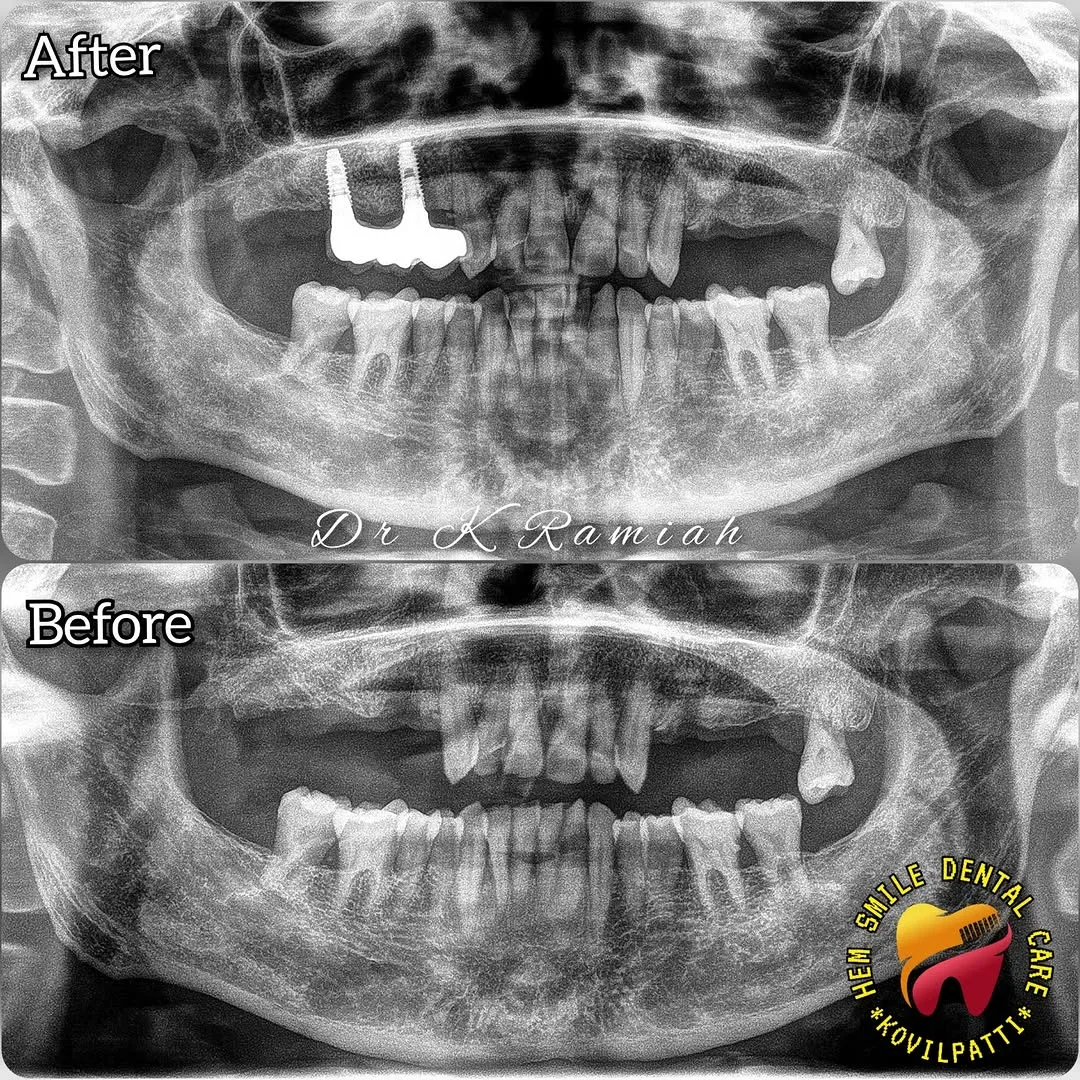

Transformations We’ve Crafted

A glimpse of our successful treatments and happy smiles at Hem Smile Dental Care.

Full Mouth Dental Implant